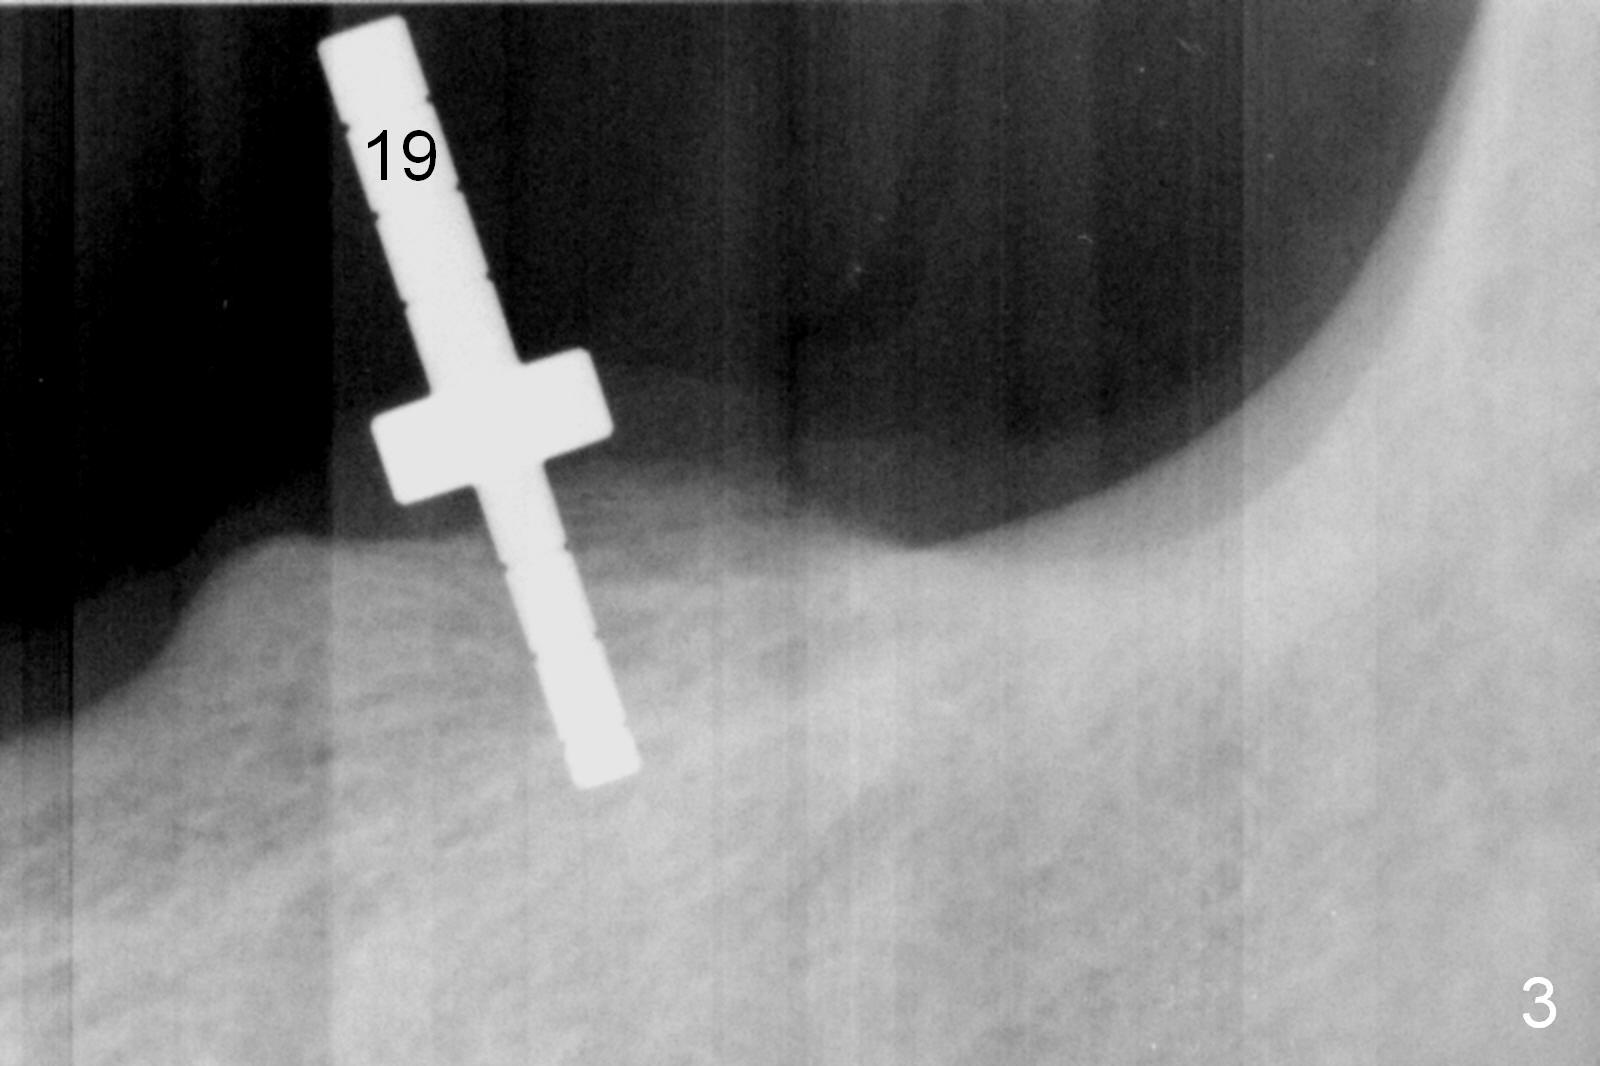

Except the tooth #30, the patient is completely edentulous (Fig.1,2). His chief complaint is "food gets into the missing tooth area". Due to short guide pin (Fig.3) and parallel pin (Fig.4), it is difficult to calculate precisely at the site of #19 the distance to the superior border of the Inferior Alveolar Canal (Fig.4 red dashed line). The clearance appears to be limited when a 4.3 mm drill is in place with 11 mm depth (Fig.5). Therefore an implant shorter than the last drill is placed (5x9 mm, Fig.6). Insertion torque is >50 Ncm. A 5x4(2) mm pair abutment is inserted temporarily to check occlusion with the opposing dentition (A). Finally a 5x2 mm healing abutment is placed with harvested autogenous bone placed between the implant and abutment (Fig.7). Before discharging the patient, the lower RPD is in place to check the position of the implant/abutment (Fig.8).